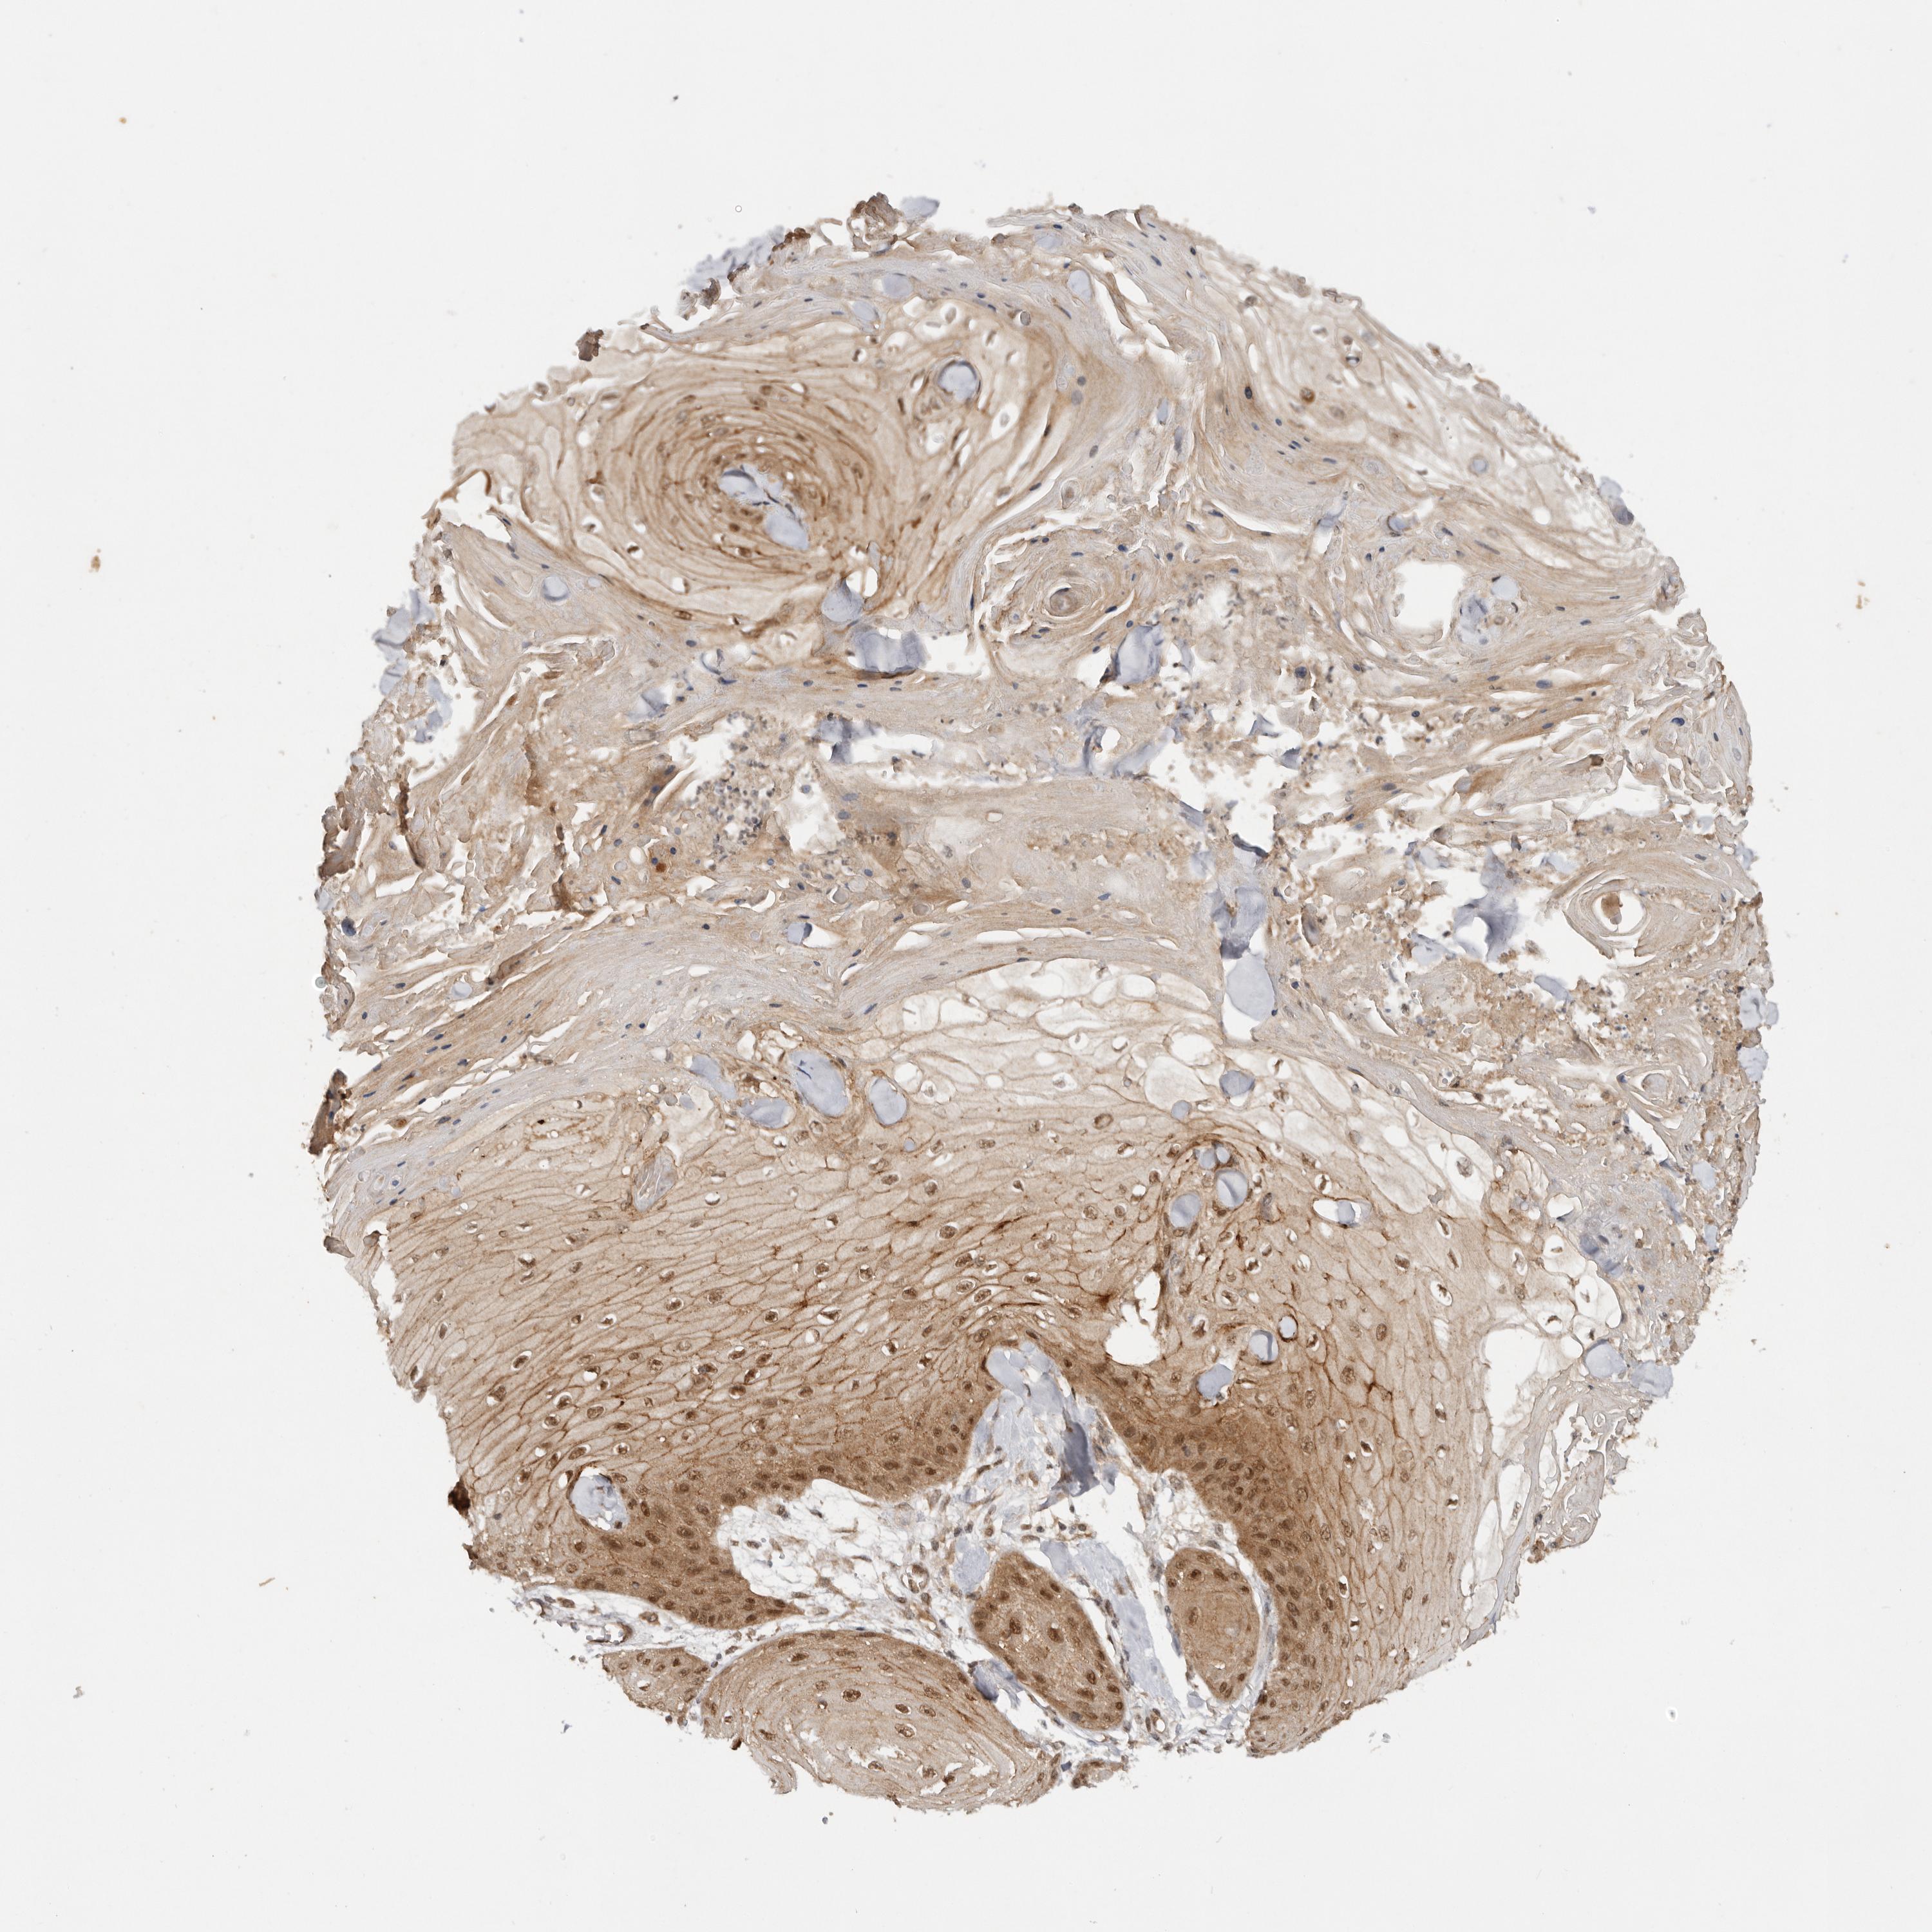

CANCER SKIN CANCER Show tissue menu

Basal cell and squamous cell cancer

SKIN CANCER - Protein expressioni

A mouse-over function shows sample information and annotation data. Click on an image to view it in a full screen mode. Samples can be filtered based on level of antibody staining by selecting one or several of the following categories: high, medium, low and not detected. The assay and annotation is described here.

Each image is clickable and will lead to virtual microscopy that enables deeper exploration of all samples and also displays staining intensity scores, fraction scores and subcellular localization as well as patient and tissue information for each sample.

Antibody HPA028626

Staining

High

Medium

Low

Not detected

Intensity

Strong

Moderate

Weak

Negative

Quantity

>75%

75%-25%

<25%

None

Location

Nuclear

Cytoplasmic/membranous

Cytoplasmic/membranous,nuclear

Basal cell carcinoma

Squamous cell carcinoma, NOS

Squamous cell carcinoma, metastatic, NOS